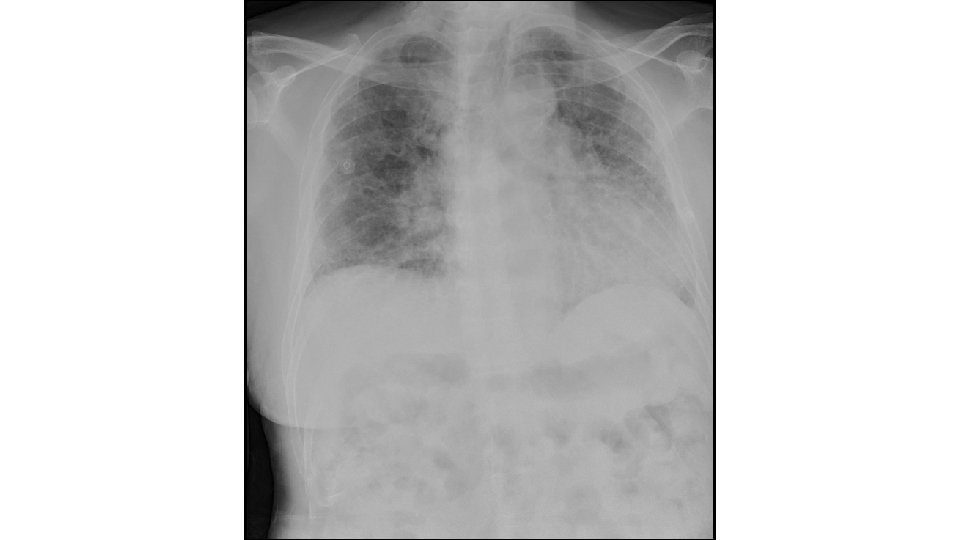

What we do Diagnostic imaging Image-guided procedures

Radiology services • Body (Abdominal) • MSK (Bone) • Breast • Cardiac • Chest • Emergency • GI/GU • Neuro • Nuclear • Pediatrics • Ultrasound • IR*